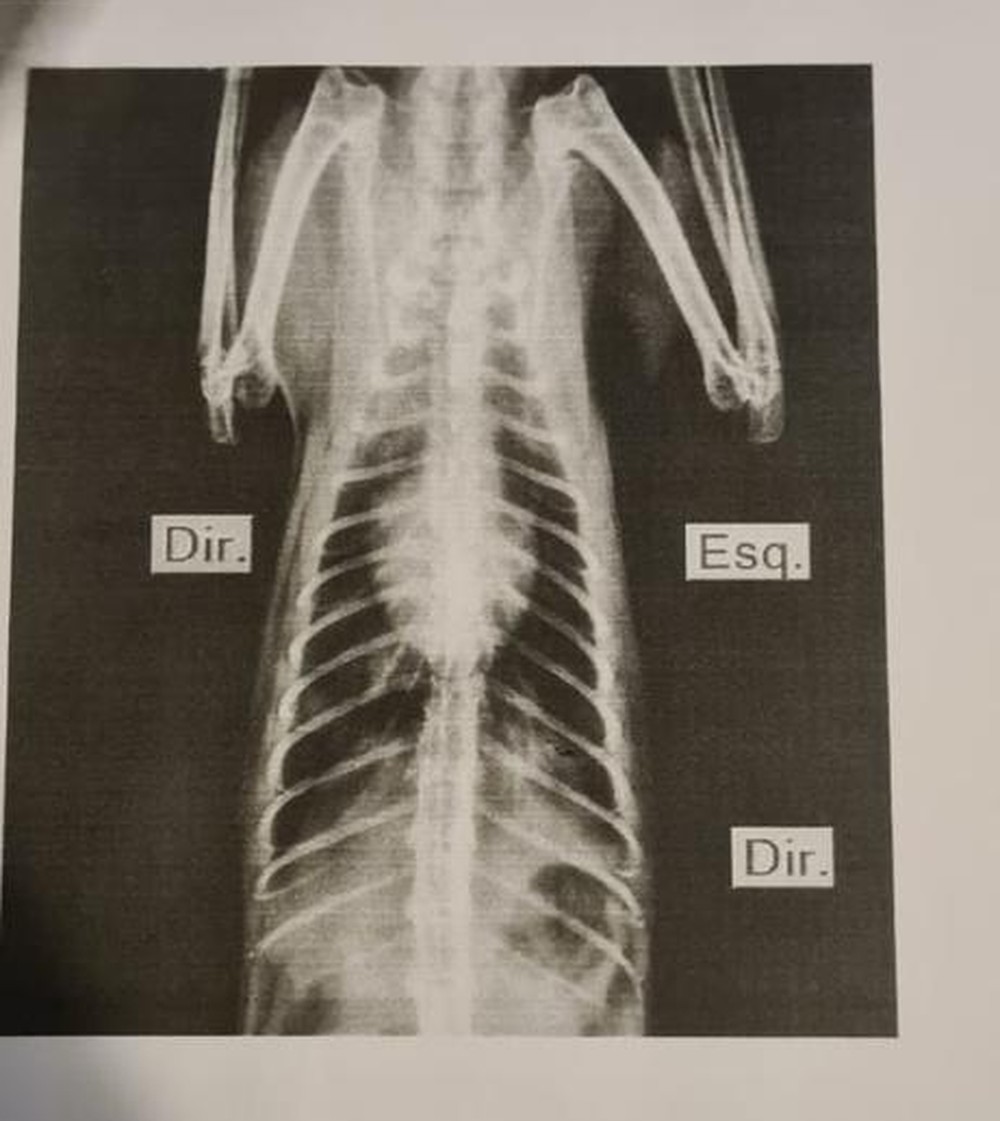

A proprietária socorreu o animal até uma clínica veterinária, onde recebeu os cuidados necessários e sobreviveu ao atropelamento. Contudo, o felino ficou com sequelas permanentes.